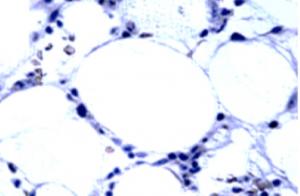

The principal research interest of Professor Inderjeet Dokal and Dr Tom Vulliamy is bone marrow failure (BMF) focusing on the genetics of the inherited BMF syndromes, particularly dyskeratosis congenita (DC). Their research has highlighted the important role of telomeres in humans and the consequences of telomere dysfunction including dysregulated human development, premature ageing, increased risk of BMF and cancer. Current research is focused on elucidating the biology of the many uncharacterized cases of DC, BMF, familial myelodysplasia/leukaemia  (with Professors Jude Fitzgibbon and Jamie Cavenagh) as well as studies aimed at correction of the cell defect with the long term aim of developing new therapies for this group of patients.